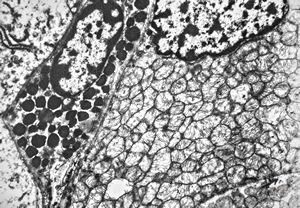

F, 44y. | carcinoid